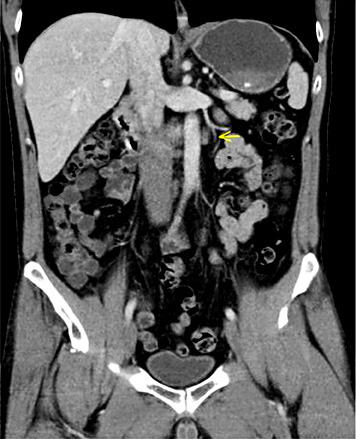

3rd patient: this 31-year-old patient underwent orchiectomy for testicular seminoma (pT3, CS1). Although markers were negative and no metastases were detected radiologically (Fig. 2a), the patient received adjuvant single-shot carboplatin therapy because of spermatic cord invasion of the primary and on grounds of personal choice of the patient. Twenty-six months thereafter he presented with a bulky retroperitoneal relapse (Fig. 2b). He was salvaged with 3 courses of BEP (bleomycin, etoposide and cisplatin) chemotherapy. It is to be noted here that the miR371a-3p level was at RQ = 3081.8 before orchiectomy and it continued to remain elevated at RQ = 351.8 five days after orchiectomy.

a Patient #3, left-sided testicular seminoma. Abdominal CT reveals unspecific small lymph node lateral to left iliac artery. Radiological diagnosis: no metastases detected. b Same patient, abdominal CT 26 months after adjuvant Carboplatin treatment: a chain of enlarged lymph nodes lateral to left iliac artery (arrows). Diagnosis: retroperitoneal relapse of seminoma.

Then, no further decrease was recorded. At the time of the clinically apparent relapse, the level had risen to RQ = 4240.3 and it decreased to normal levels at the completion of salvage therapy and remained stable during the later course. This case was briefly reported previously [13].